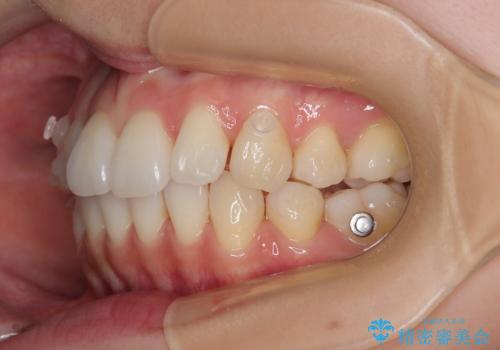

1. 抜歯矯正の軽度後戻りを解消 インビザライン矯正の治療前

2.

3. 抜歯矯正の軽度後戻りを解消 インビザライン矯正の治療後